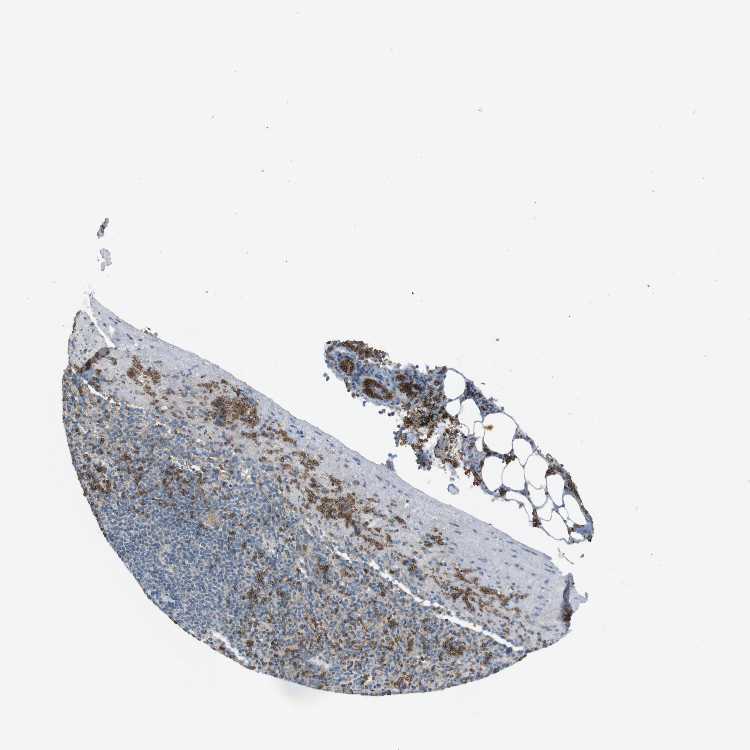

SPLEEN - Antibody stainingi

Antibody staining in the annotated cell types in the current human tissue is reported as not detected, low, medium, or high, based on conventional immunohistochemistry profiling in selected tissues. This score is based on the combination of the staining intensity and fraction of stained cells.

Each image is clickable and will lead to virtual microscopy that enables deeper exploration of all samples and also displays staining intensity scores, fraction scores and subcellular localization as well as patient and tissue information for each sample.

Antibody HPA014811Antibody CAB002658

Cells in red pulp LowNot detected

Cells in white pulp Not detectedNot detected